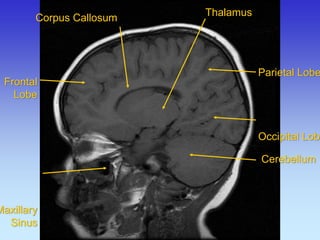

Corpus Callosum

Thalamus

Cerebellum

Frontal Lobe

Temporal

Lobe